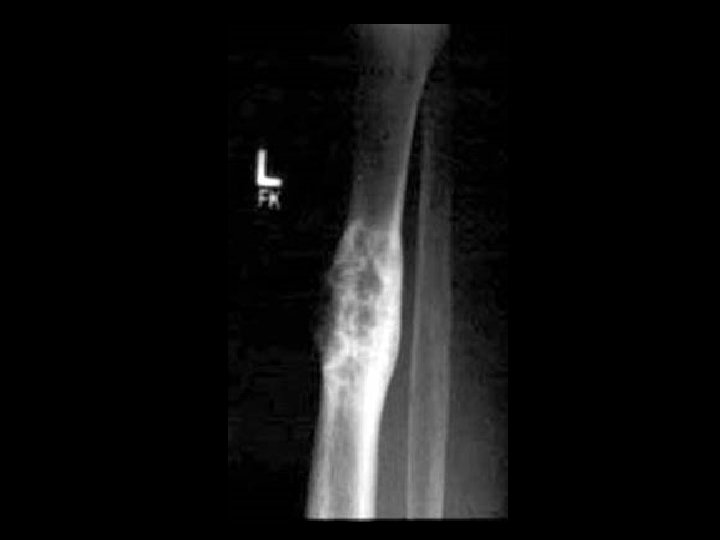

Adamantinoma • Findings: – Expansile mixed lytic and sclerotic lesion of the tibial midshaft – Cortical disruption and periosteal reaction • ddx: – Fibrous dysplasia